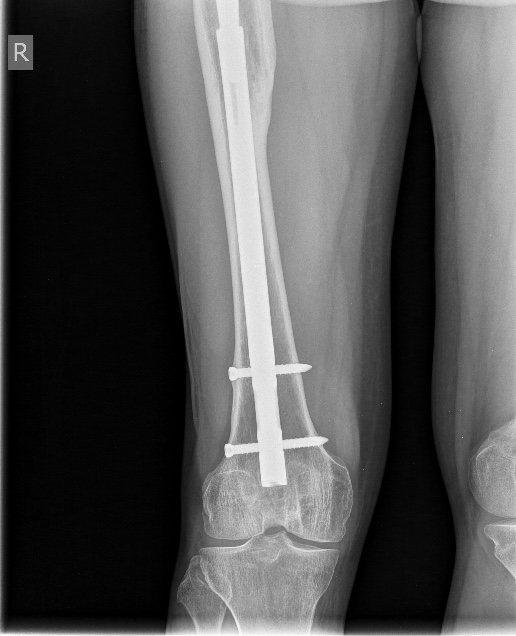

[Ortho] Перимплантный перелом бедра

Закрытое штифтование с удлинением бесцементной ножки при переломах

Vancouver B2/ B3 дает неожиданно для приверженцев традиционной догмы

хорошие результаты.

Здесь  - http://weborto.net/forum/1256380983/ -  первое наше наблюдение

такого остеосинтеза с нестабильной ножкой. Прошло уже 6 лет - вот

недавние снимки. Пациент не имеет жалоб, катается на коньках. Никакие

дистальные винты не выдержали бы циклических нагрузок столько лет, если

бы ножка оставалась нестабильной.